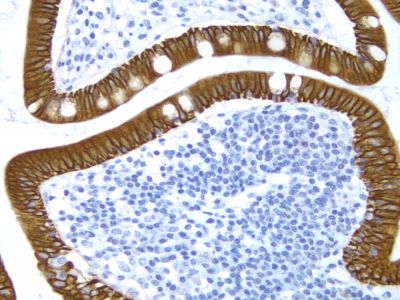

ImmPACT AMEC Red HRP Substrate utilizes Vector Laboratories ImmPACT technology to generate a crisper, brighter red reaction product that is 5 -10 times more sensitive than conventional AEC substrates and can be used as a single label or as a second color for multiple antigen labeling.

| Chromogen Color | Red |

ImmPACT AMEC Red chromogen can be used for both manual and automated staining methods. Stained slides must be aqueously mounted because the reaction product is soluble in organic solvents. Precipitated ImmPACT AMEC Red is stable for at least 2 years when mounted in VectaMount? AQ (H-5501).